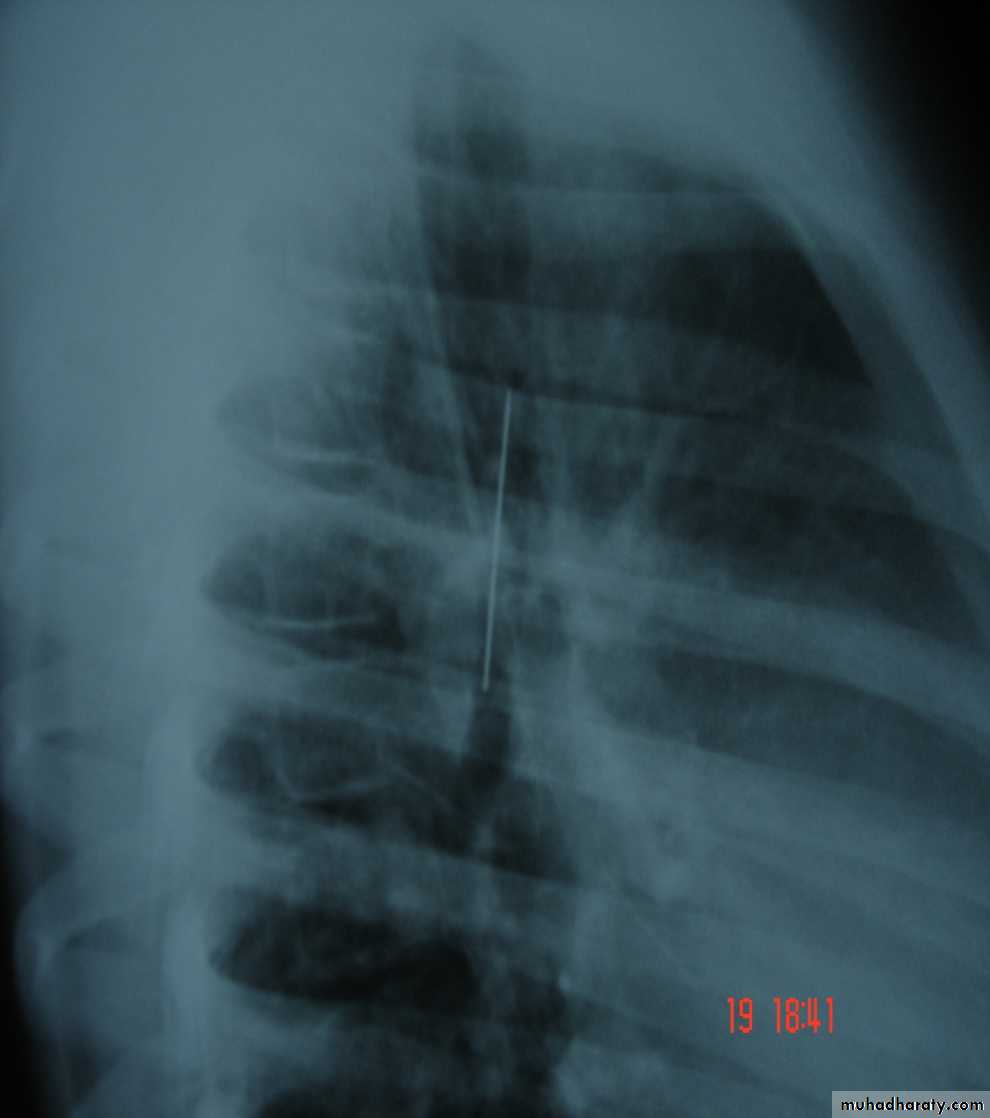

• Pneumothorax , bronchospasm , Bronchial perforation (Surgical emphysema & tension pneumothorax ) ,

• 3-Some may advise routine CXR after performing a biopsy to check for signs of pneumothorax .